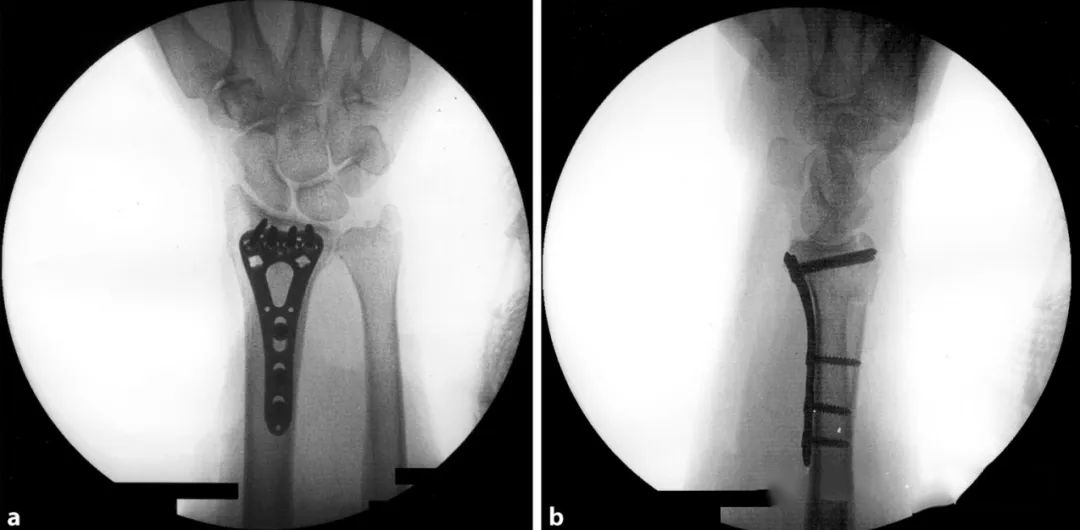

В настоящее время для оценки репозиции и положения винта используется внутренняя фиксация ладонной анатомической фиксирующей пластиной.Запястье приподнимается, чтобы компенсировать ладонный наклон и локтевую девиацию и избежать перекрытия суставных поверхностей: